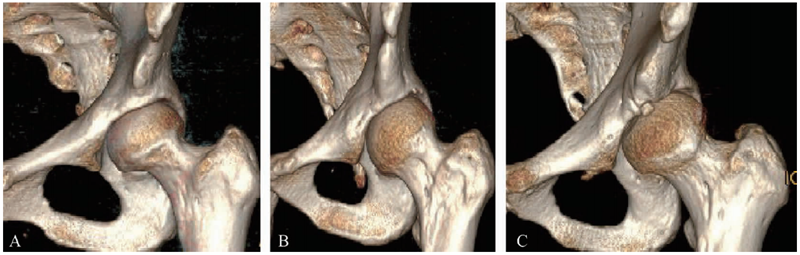

AIIS的位置和形态与SSI的形成密切相关,Hetsroni通过CT三维重建对AIIS的形态进行了临床分型(图1):Ⅰ型AIIS,其下缘和髋臼骨性边缘界限清晰并存在平缓的髋臼骨壁;Ⅱ型AIIS,其下缘延伸到髋臼骨性边缘,两者界限难以分清;Ⅲ型AIIS,其下缘向下突出超过髋臼骨性边缘。Ⅱ和Ⅲ型AIIS可能导致髋关节屈曲和内旋活动度受限,也可能是盂唇损伤的潜在解剖因素。

图1 AIIS的形态差异和临床分型A.Ⅰ型;B.Ⅱ型;C.Ⅲ型